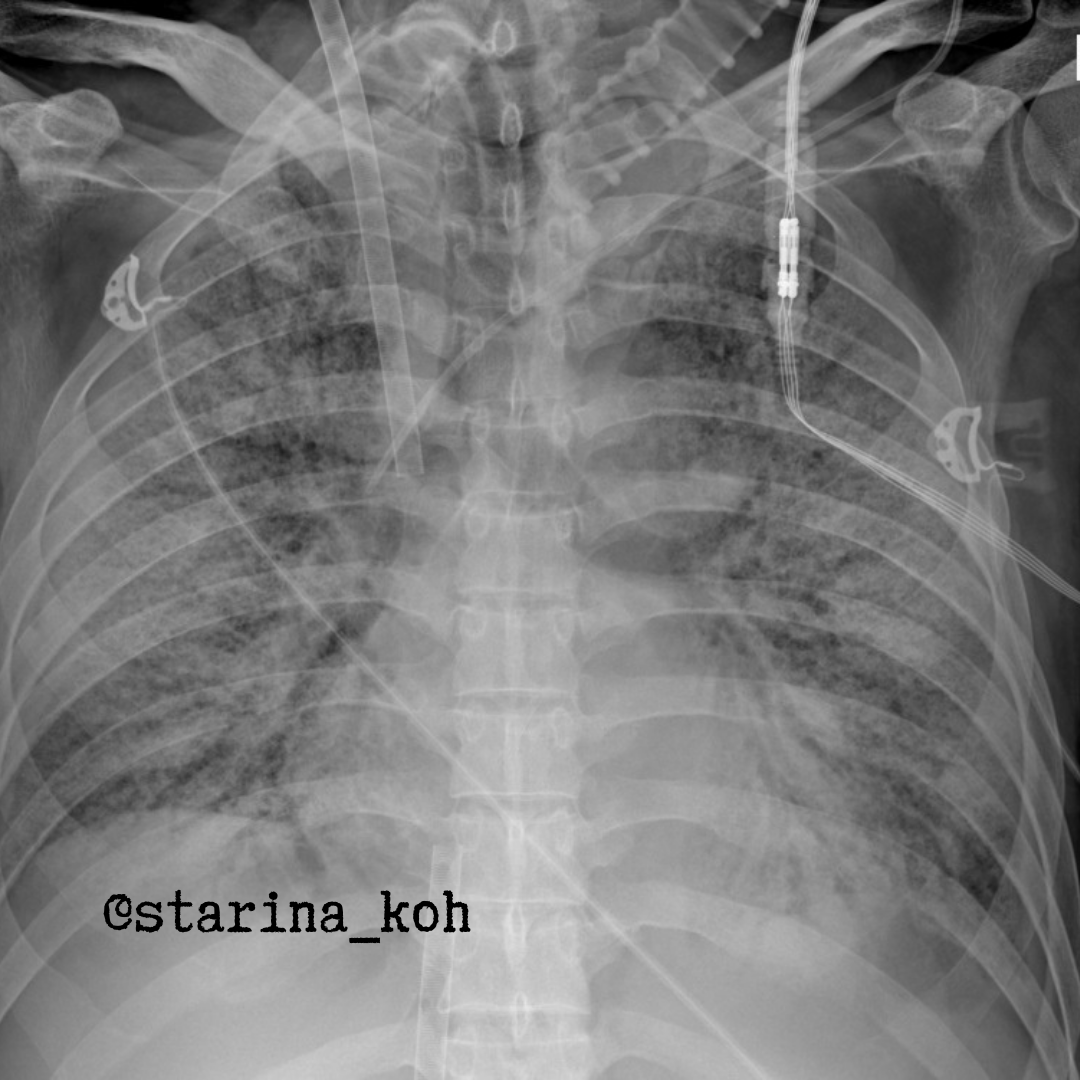

В легких по данным КТ ОГК - участки уплотнения по типу "матового стекла" невысокой интенсивности (от 09.08).

В настоящее время именно такой "идиопатический ОРДС" носит название синдрома Хаммана-Рича. В определенный момент этиологический фактор ОРДС уже не столь важен - т.к. от большинства вирусов не существует этиологической терапии, поэтому приходится коррелировать следствия в виде подавления избыточной иммунной реакции и поддерживать адекватную оксигенацию. Т.к. у данного пациента не удалось достигнуть адекватных параметров оксигенации путем ИВЛ, в т.ч. в прон-позиции, пациент был переведен в специальный центр ЭКМО, где и была инициирована VV-ЭКМО - вы можете видеть характерную постановку канюлей на рентгеновском снимке.